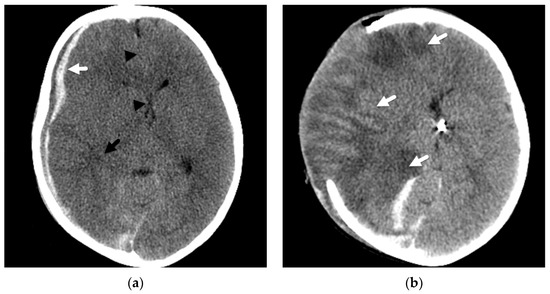

2. Patterns of Diffuse Parenchymal Insults

3. Imaging of Diffuse Insults